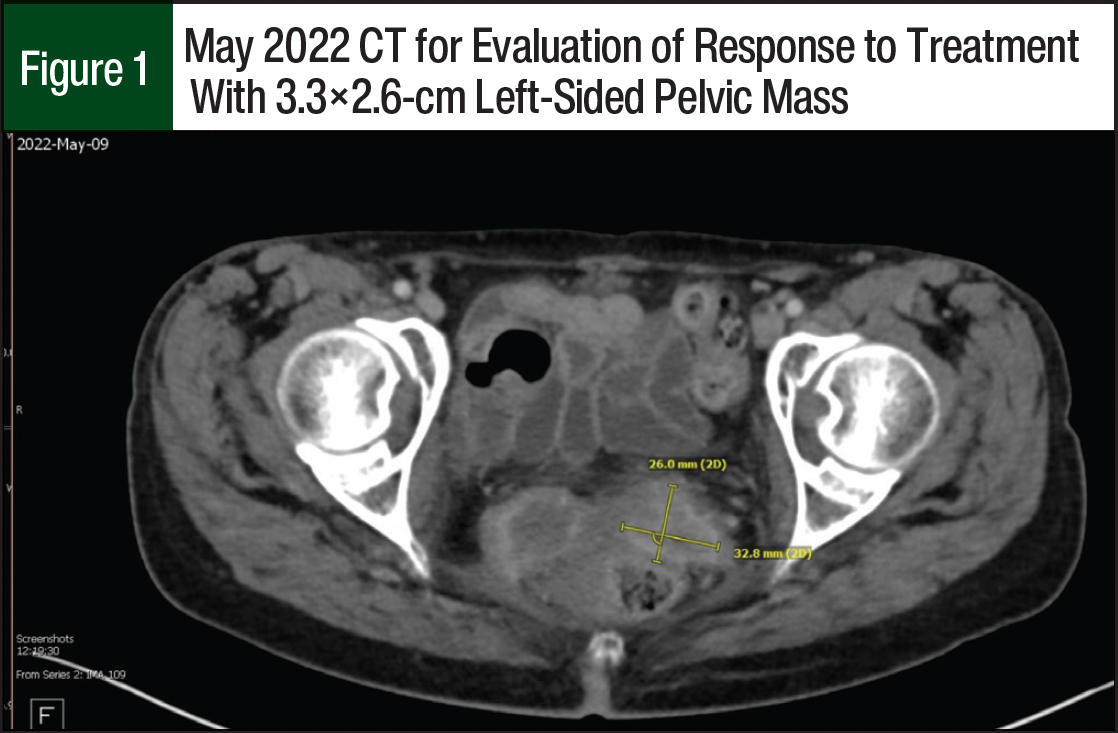

A restaging CT in May 2022 showed small progression of disease with a left-sided pelvic mass measuring 3.3×2.6 cm (Figure 1) and a right-sided pelvic mass measuring 3.7×3.5 cm. The team considered the patient to have stable disease, and the patient received an additional 6 cycles of pembrolizumab. In August 2022, a restaging positron emission testing/CT showed a continued increase in the size of the right-sided pelvic mass now measuring 6.9×4.4 cm; and the pulmonary metastases were not metabolically active. Because of this pelvic disease progression, tisotumab vedotin was added to the current therapy.

The patient started receiving treatment with tisotumab vedotin 2 mg/kg and pembrolizumab 200 mg IV every 3 weeks. After 6 cycles of the new regimen, a CT scan showed her left-sided pelvic mass decreased in size and now measured 2.9×1.2 cm (Figure 2) and that there was no new metastatic disease. Another CT scan was obtained after an additional 4 treatment cycles, which showed an interval increase in the left-sided pelvic mass that now measured 4.5×2.8 cm (Figure 3), and an unchanged pulmonary nodule signifying that her distant disease appeared to be well controlled. The patient continued systemic treatment and was referred to interventional radiology for pelvic embolization. To date, the patient has received 12 treatment cycles of tisotumab vedotin and pembrolizumab. She has tolerated the regimen well and only had mild dry eye; laboratory testing showed that she also had hypomagnesemia and hypokalemia.